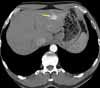

Given the patient's age and history of diabetes, atherosclerotic arterial narrowing is suspected. Liver and kidney function test results and a complete blood cell count are normal. A contrast-enhanced abdominal CT scan reveals no aortic aneurysm or kidney abnormality; however, 3 lesions are noted in the liver. A CT slice shows the largest lesion, located in the left lobe of the liver (Figure 1).